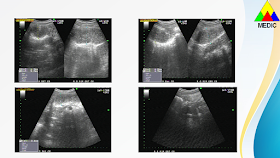

Ultrasound detects a cystic mass # 17.9x11.2 centimeter from his navel to pubis, and jejunum dilatation with obstruction sign (washing machine sign). The cystic mass contents fluid and septation with vascular sign on its walls. The cause of bowel obstruction was noted by a non-dilated bowel loop at the mesenteric root with whirpool sign.

There is not  bowel malrotation nor duplication cyst, so the ultrasound findings is bowel volvulus due to a mesenteric cyst.

MSCT confirms bowel volvulus due to a mesenteric cyst later.